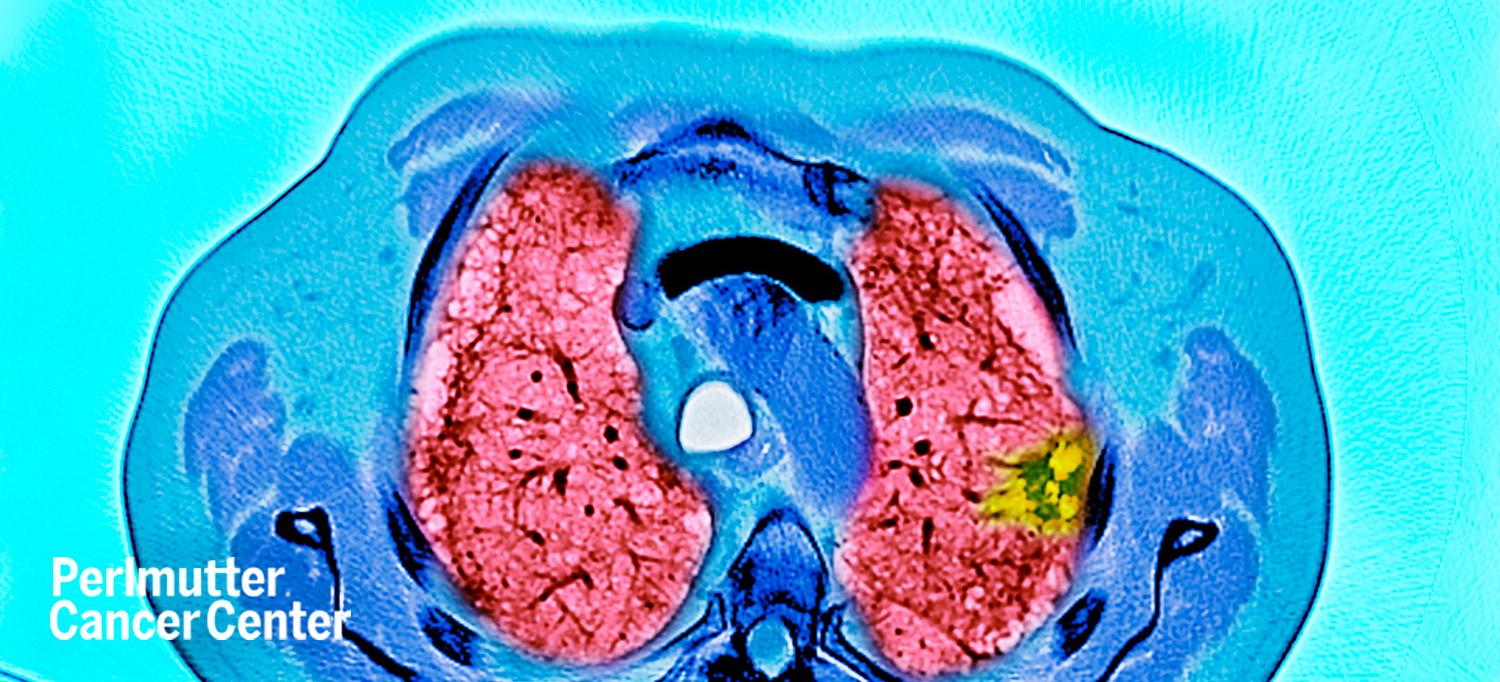

Photo: DR P. MARAZZI/SCIENCE PHOTO LIBRARY/Getty

For those who qualify for testing, the initial screening involves a low-dose CT scan. If a growth or nodule is detected, follow-up screening may include advanced techniques such as navigational bronchoscopy, endobronchial ultrasound, or needle biopsy, to determine the best course of treatment.